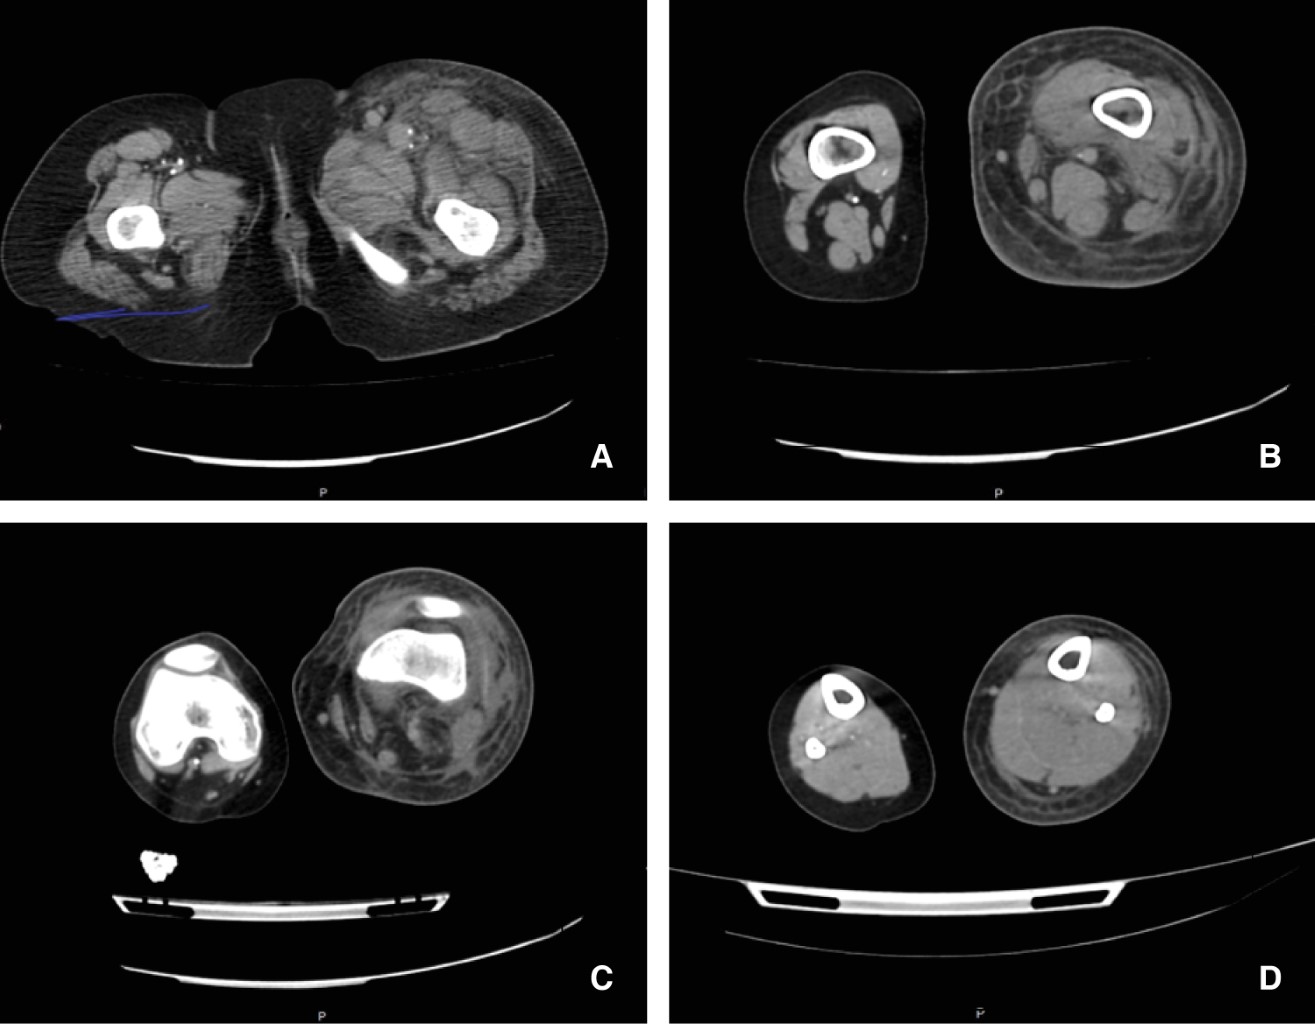

El análisis del electrocardiograma evidencia taquicardia sinusal sin otra alteración. Radiografía de tórax sin lesiones. Ante la sospecha de trombosis arterial se solicita ultrasonido Doppler de emergencia que reporta trombosis venosa profunda y superficial de miembro pélvico izquierdo, arteria iliaca externa permeable, arteria poplítea izquierda presentando flujo en su interior, no audible y sin espectro Doppler (Figura 2). Se realiza angiotomografía contrastada que evidencia edema de tejidos blandos, disminución del calibre de arteria femoral del lado izquierdo en tercio medio y distal, sin paso de contraste a partir de la arteria poplítea, trombosis venosa superficial y profunda en extremidad izquierda, extremidad derecha sin alteraciones (Figura 3). Tomografía de cráneo sin evidencia de patología (Figura 4). Inicia manejo con anticoagulación (enoxaparina), pentoxifilina, terapia hídrica con soporte con aminas vasoactivas (adrenalina y dobutamina) y antibiótico de amplio espectro (ceftriaxona), además de transfusión de hemoderivados e ingreso a Unidad de Terapia Intensiva Pediátrica.